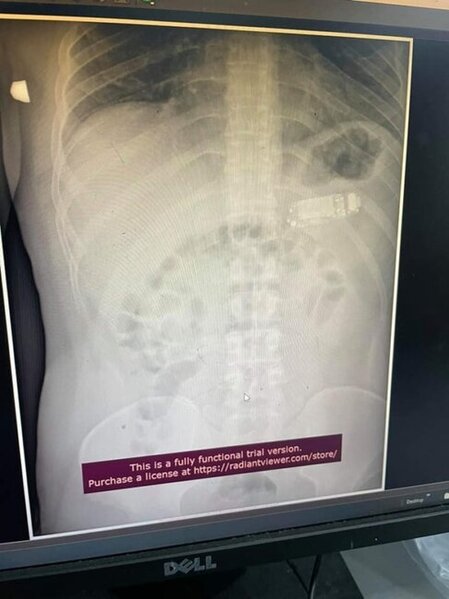

Həkimlər ŞOKDA: Mədəsindən TELEFON ÇIXDI - FOTO

Misir klinikalarından birində xəstənin mədəsindən telefon çıxıb.

Sonxeber.az BiG.AZ-a istinadən xəbər verir ki, klinikaya müraciət edən şəxs qarnındakı ağrılardan şikayətlənib.

Rentgen müayinəsi zamanı onun mədəsində mobil telefonun olduğu məlum olub.

Pasiyent telefonu 6 ay öncə udduğunu etiraf edib, lakin bunun səbəbini açıqlamayıb. O, utandığından həkimə müraciət etmədiyini və telefonun təbii yolla xaric olacağına ümid etdiyini bildirib.

Lakin yad cism bədənə daxil olan qidanın qarşısında maneəyə çevrilib, həzm sistemində problemlər yaradıb və ağrılarara səbəb olub.

Həkimlər əməliyyat vasitəsi ilə telefonu xəstənin mədəsindən çıxarıblar.